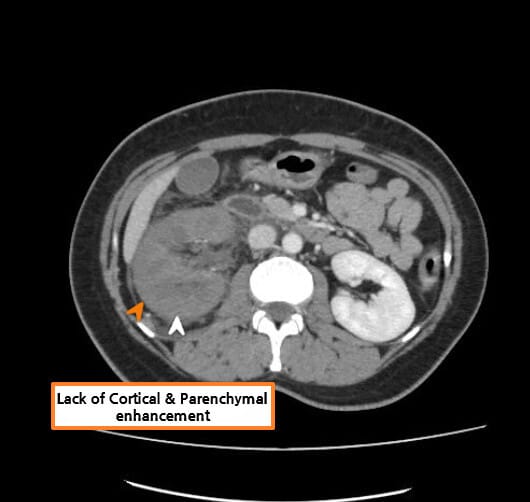

| CT 소견 |

| 🔴 신장 정맥에 filling defect 또는 혈류 차단 |

| 조영증강 CT 또는 MRI에서 신정맥 내 결손 음영이 보이며, 혈류가 차단된 모습이 나타날 수 있습니다. |

| 🔴 비대칭적 신장 크기 |

| 신정맥 혈전증이 동반되면 혈전이 발생한 쪽 신장이 비대해지고, 혈류가 감소합니다. |

Abdrabou A, Renal vein thrombosis. Case study, Radiopaedia.org (Accessed on 23 Jul 2025) https://doi.org/10.53347/rID-51291